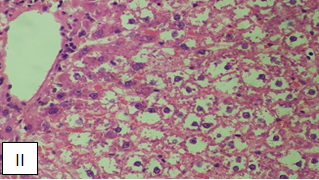

Intoxicated group showing severe hepatocytes degeneration and ballooning. Liver architecture is disturbed

BLEE group (Ethanol+BLEE 400 mg/kg) showing normal liver architecture, minimal vacuoles in hepatocytes and normal Sinusoids. (H and E 40X)

Fig. 5: Histopathological studies